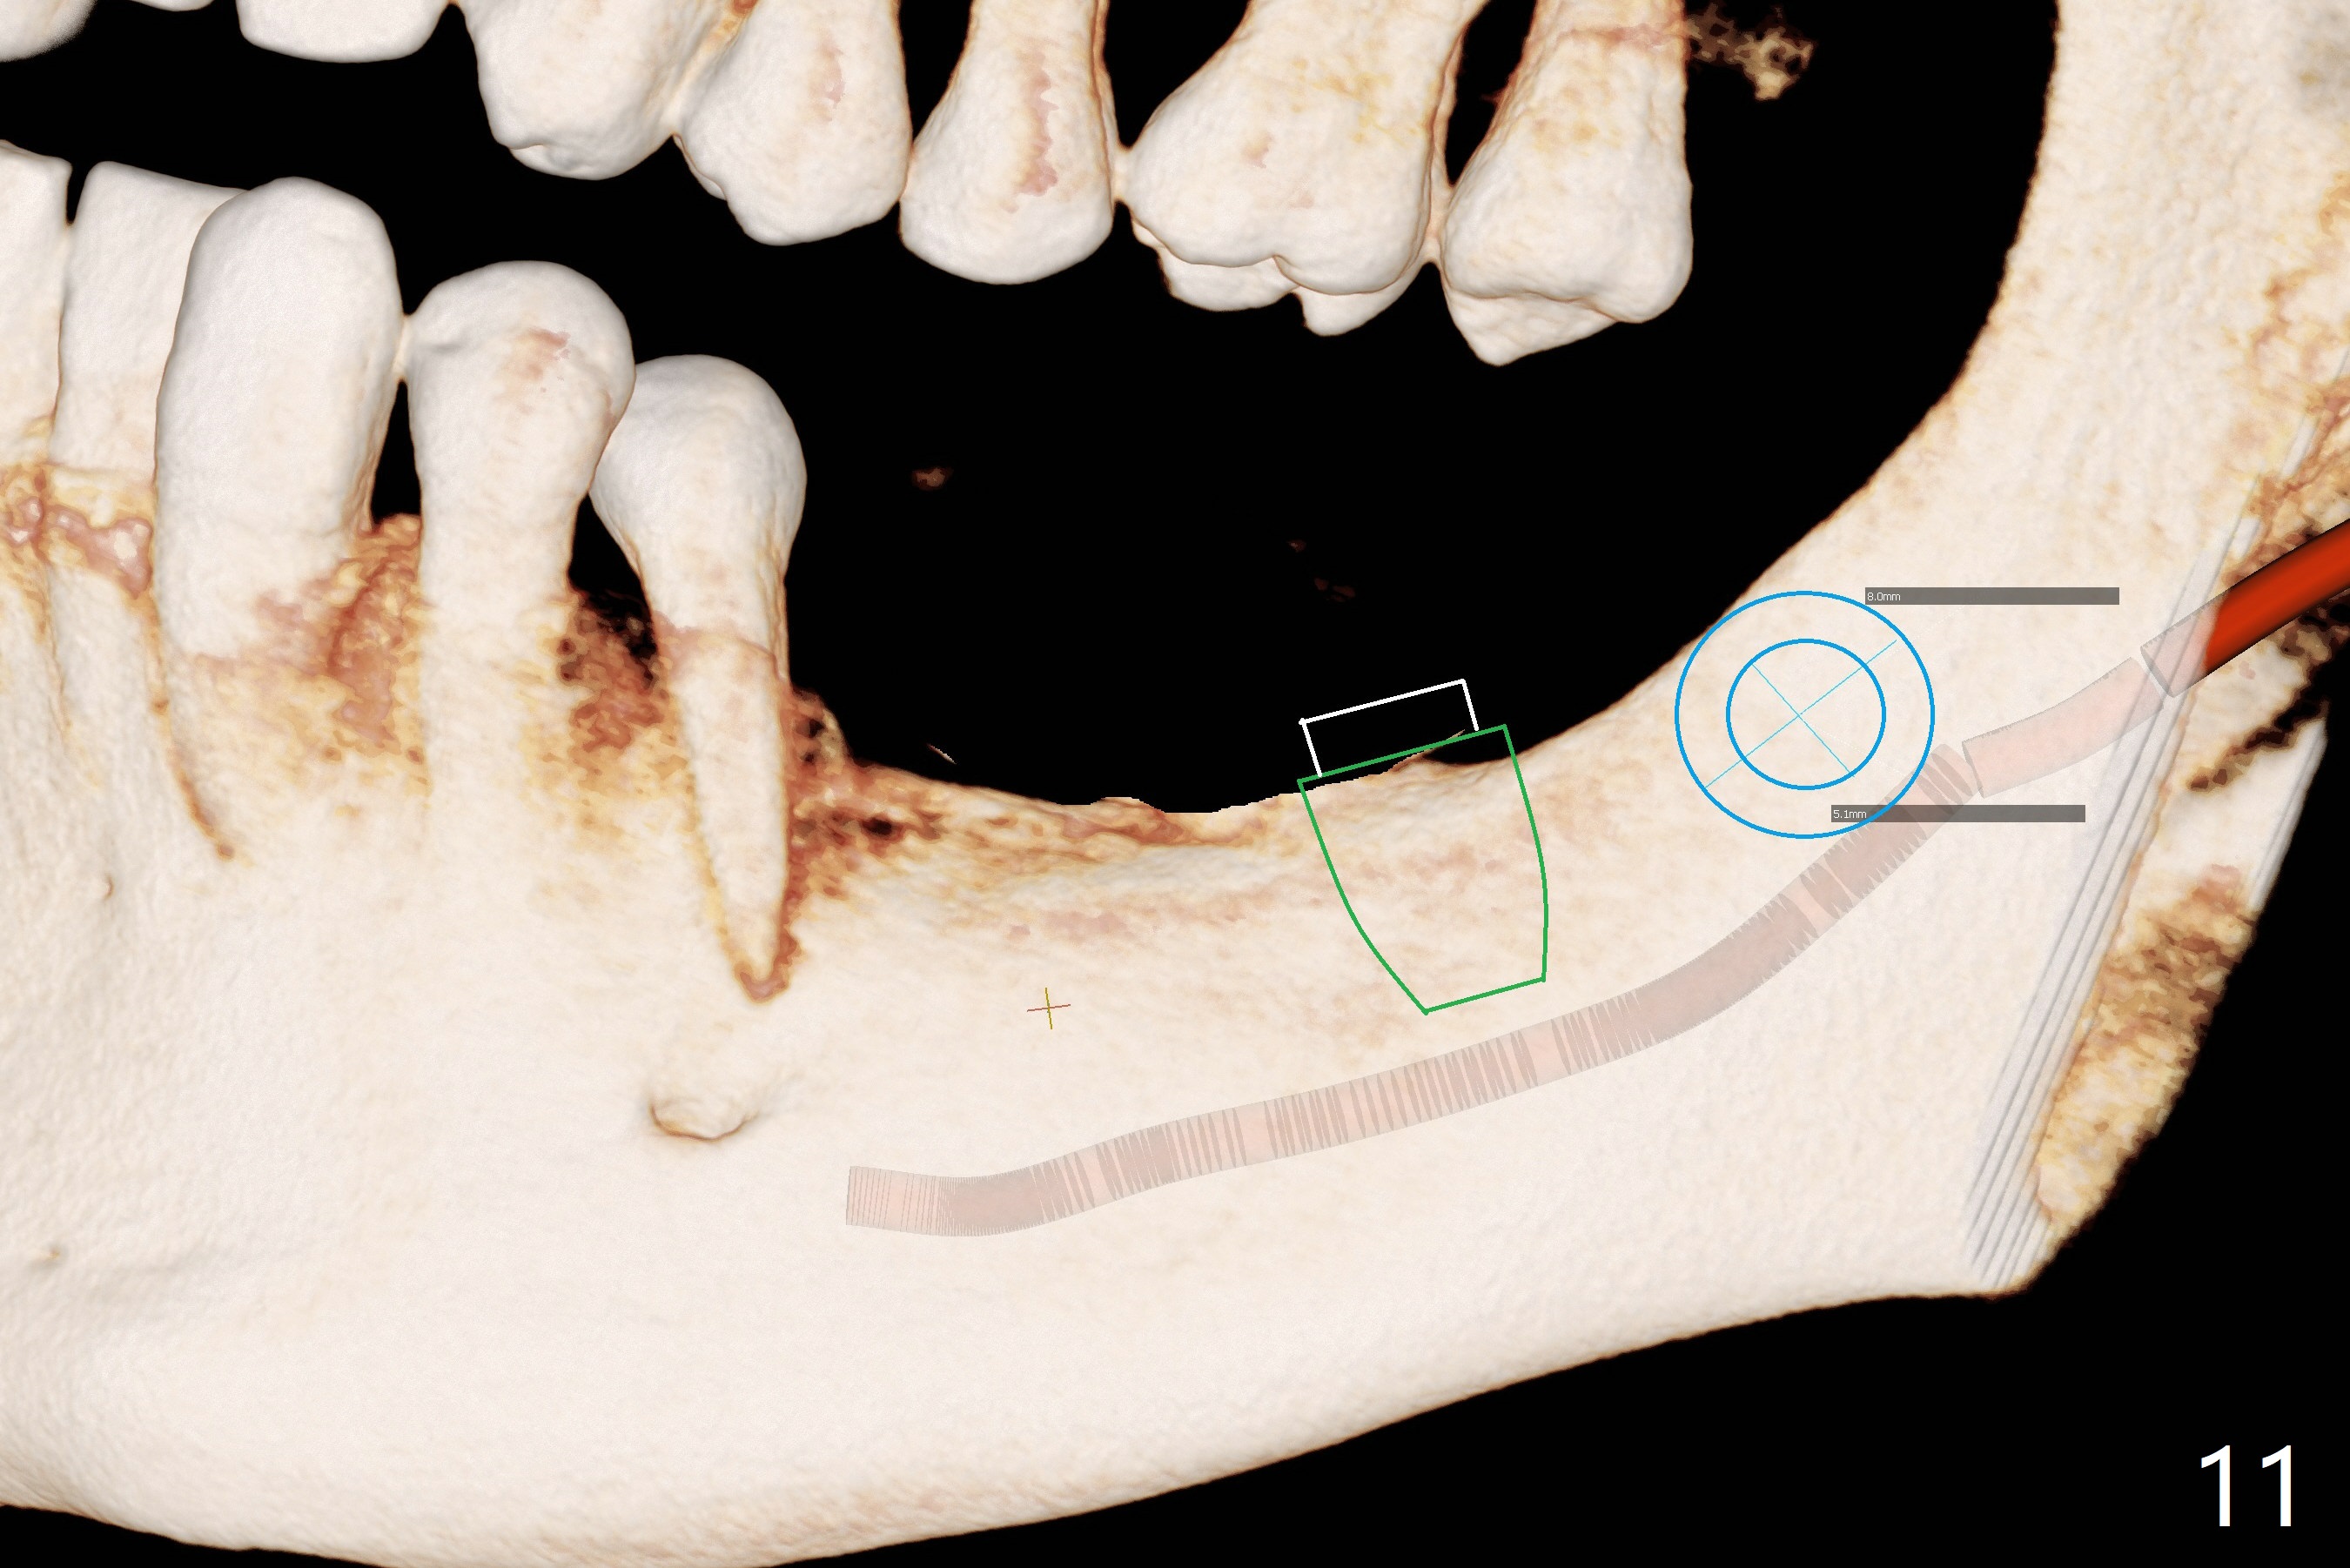

Preop photo shows severe mesial tilt of the tooth #18 (Fig.1). After extraction, the osteotomy is established in the apical end of the socket, where the buccolingual width is limited. It appears that an extra wide implant (5.9 mm) may perforate one of buccolingual plates. On the other hand, the buccal plate (Fig.2 double arrows) is intact and approximately 2 mm tall, whereas the lingual one is thin and lower. Initial osteotomy confirms that bone heights at #18 and 19 are 6 and 8 mm, respectively. Counting 2 mm of the buccal plate and bone graft lingually, a 8 mm long implant may be a practical option at the site of #18. After initial placement of two of 5x8 mm SM implants (Fig.3), the depth of the implant at #19 is adjusted twice (Fig.4,5). With placement of autogenous and allograft (Vanilla, Fig.5 *)) and abutments, a piece of cotton pellet is placed in each abutment well (access, Fig.6 *). Periodontal dressing is applied to the abutment wells for additional retention (Fig.7 *). Due to local poor oral hygiene, splinted provisional is fabricated 4 months postop (Fig.8) in preparation for limited orthodontic uprighting the tooth #20. The patient has pain with mastication at #18 eleven months post cementation (Fig.9). It appears that both of the implants should be removed with immediate replacement and bone graft. Prepare 4 PRF and sticky bone. The new implant will be 5.0 or 5.5x5 mm (Fig.10 green) with 2.3 mm platform (white). A block graft will be harvested from the ipsilateral ramus using 9/8 and 6/5 mm trephine burs for 2-3 mm in depth (Fig.11 blue). The ring graft will be seated around the platform over the implant (Fig.12).